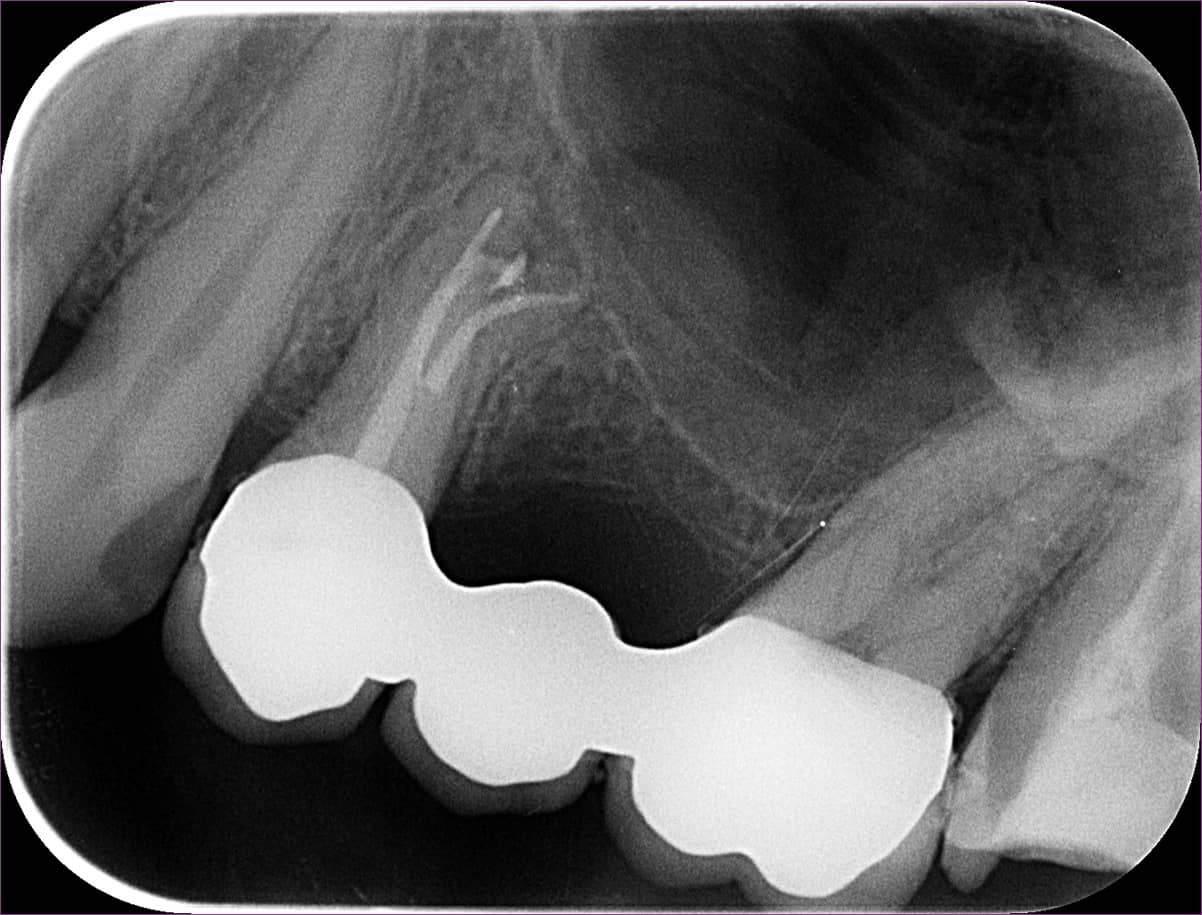

A gyökérkezelés menete szerint ezután kerül sor a gyökértömésre. A gyökértömésről készült felvételen nagyszerűen látszik egy ilyen oldalcsatorna teljes feltelítődése: ezt nyilakkal jelöltük.

Ezen az utolsó képen látható a fog kontrollfelvétele. A gyökértömést követően a fogat üvegszálas-csapos megerősítéssel láttuk el, majd a gyökérkezelés menete az utolsó fázisához ért: a kezelőorvos beragasztotta az elkészült fogászati hidat.